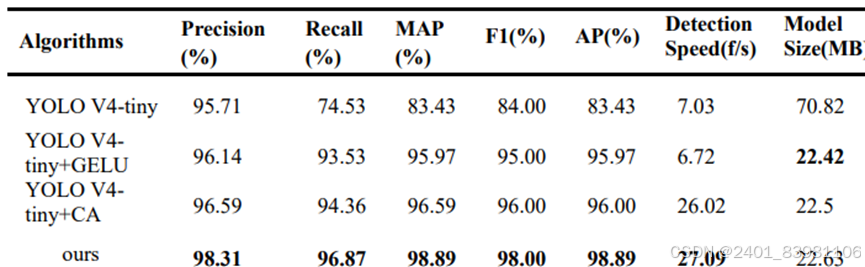

几种算法检测对比示例

如改进的 YOLO V4-tiny 舌像定位检测算法,更适于小目标检测(K-Means ,模糊C均值)但精度,速度低(已改进GCYTD 算法) 采用粗分割网络 Rsnet定位舌体,精分割网络Fs-net对定位的舌体进行精细分割,最高F值超过99%。